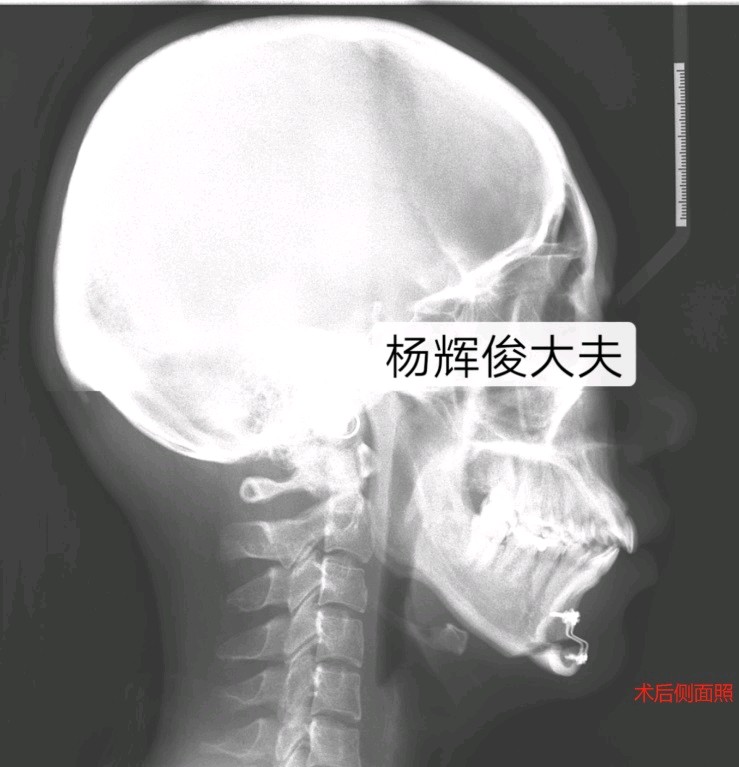

一、颏成形术

口内进路的水平截骨颏成形术是矫正各种颏部畸形的基本术式,无论是作为正颌外科的辅助手术,还是作为独立的面部整形美容手术,其应用越来越普遍。也是目前矫治各种颏部形态异常的最佳手术。

缺点:需要住院治疗,手术需要专业熟练的口腔颌面外科医师完成;由于术中暴露及不适当的牵拉,可能造成颏神经的损伤而导致术后较长时间的下唇颏部麻木及不适感。